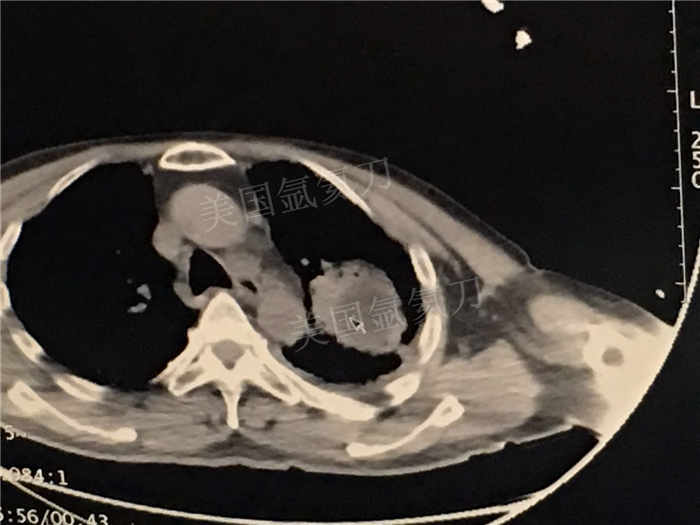

下一篇:中日友好医院氩氦刀冷冻消融治疗胸膜间皮瘤